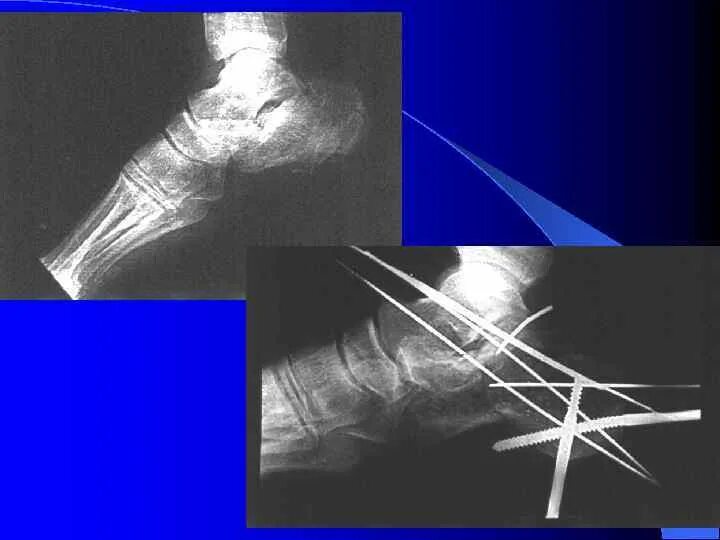

Остеосинтез мрт